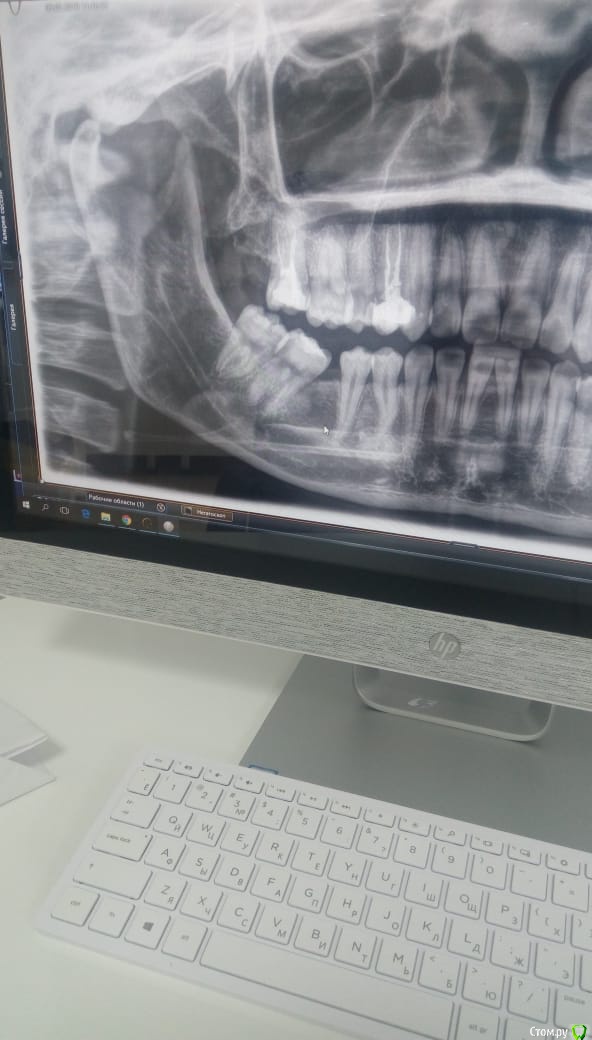

Daniyar Опубликовано 12 февраля, 2019 Поделиться Опубликовано 12 февраля, 2019 FYI 4 Ссылка на комментарий

red_butler Опубликовано 15 февраля, 2019 Поделиться Опубликовано 15 февраля, 2019 Виновница подчелюстной . Не нашел тему с 8ками - была раньше популярна. http://forum.stom.ru/topic/20438-galereia-vosmerok/ Ссылка на комментарий